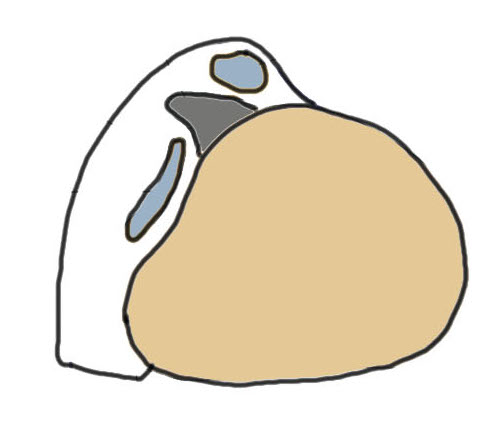

1. Injury to superior peroneal retinaculum (SPR) / fibrocartilaginous ridge (FCR)

Peroneal tendons sublux out of grove

| SPR detaches from FCR | SPR and FCR detached | Bony avulsion of SPR and FCR | Midsubstance rupture of SCR |

Anterior subluxation of peroneal tendons

Anterior subluxation of peroneal tendons